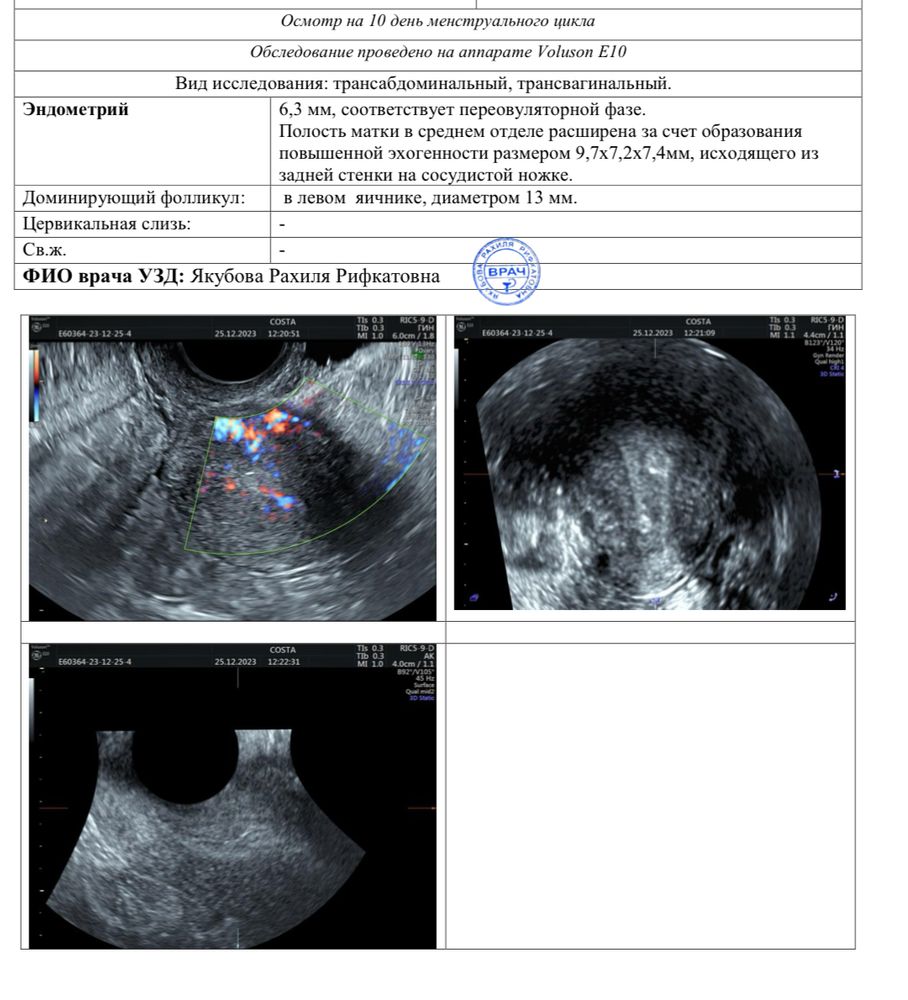

ЭКО(Протокол,подготовка)Девочки, очень нужна поддержка и отзывы в схожей со мной ситуации 🙏🏻 у кого находили полип эндометрия перед вступлением в протокол ЭКО, как скоро вы восстановила и вошли в протокол? У меня нашли сегодня довольно большой полип на 10 д.ц. 😞 В январе ждала вступление в протокол ЭКО.